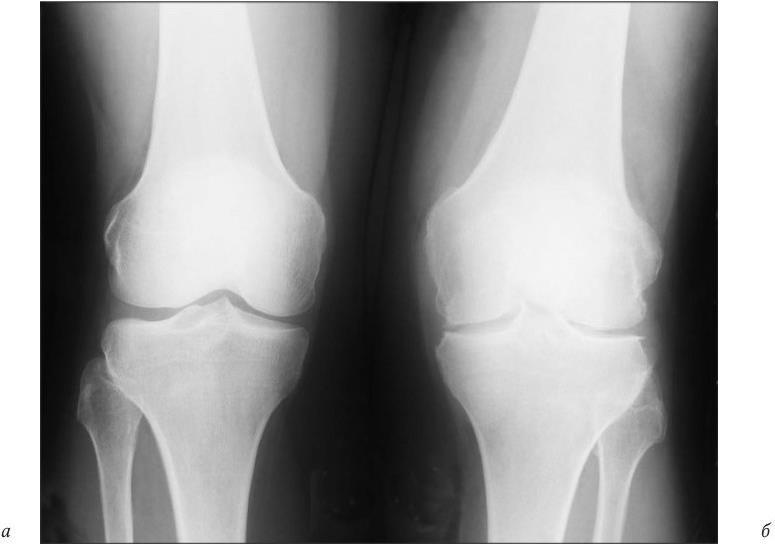

Рентгенография выявляет при этой форме, наряду с остеофитами, околосуставной остеопороз, немногочисленные эрозии. На рис. 19 представлена рентгенограмма больной пожилого возраста (сочетание ОА и РА). Можно видеть как окостеневающую хондроидную ткань (остеофиты), так и резко выраженное, не свойственное ОА разрежение костной ткани и краевые дефекты костей — эрозии.